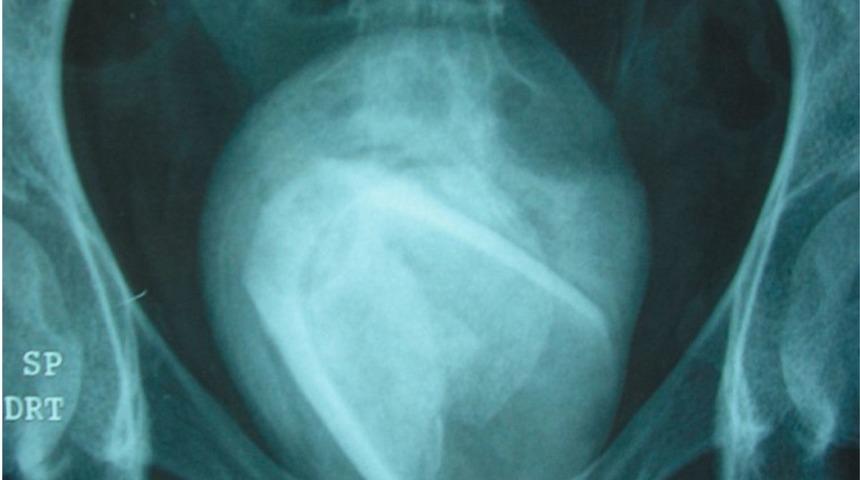

Doktorların çektiği röntgende mesanesinin içinde bir cam parçası olduğunu fark ettiler. Tıp uzmanlarının açıkladığı raporda, kadının birkaç yıl önce cam bir cinsel ilişki oyuncağını vajinasının yerine idrar yolunda hareket ettirmesi sonucunda bir parçanın o kısımda kaldığını anladılar. Doktorlar, tıbbi prosedürde üretradaki tıkanıklıkları temizlemeye yardımcı oldular.